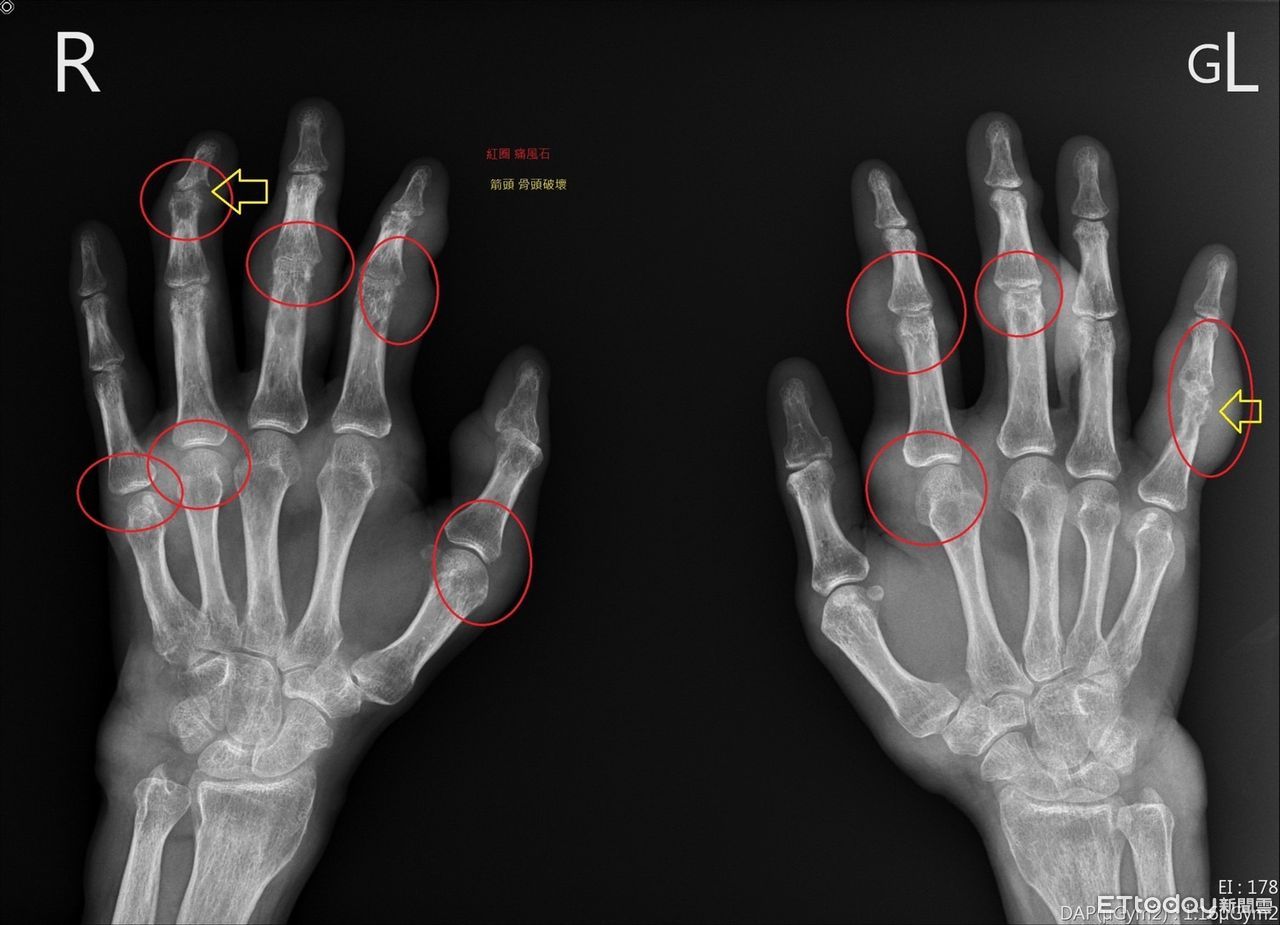

▲痛風患者手部X光片,紅圈為痛風石,黃色箭頭為遭破壞骨頭。(圖/慈濟醫學中心提供,下同)

痛風是一種急性的關節炎,症狀包括關節紅腫、發熱、劇烈疼痛,主要發生原因是尿酸結晶累積在關節,時間久了甚至引發急性痛風性關節炎、長痛風石,潘郁仁醫師說,痛風石通常是長在常發作的關節位置,包括手指、腳趾、膝蓋、手肘、腳踝,很多人發作時痛到無法行動要請假。

▲潘郁仁醫師說,痛風石通常是長在常發作的關節位置,包括手指、腳趾、膝蓋、手肘、腳踝,發作時痛到無法行動要請假。